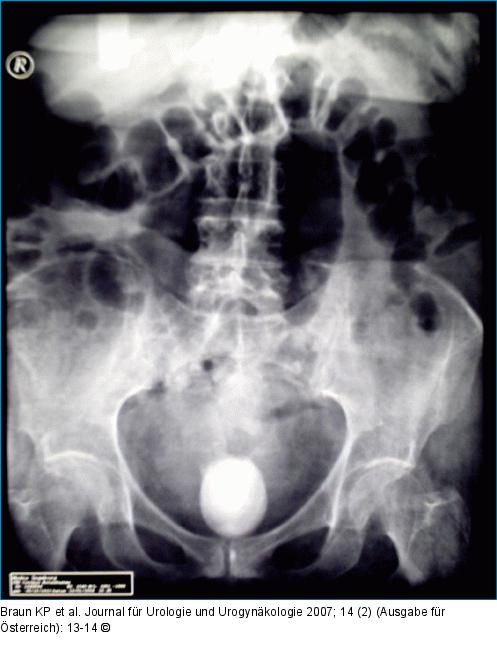

Abbildung 1: Abdomenübersichtsaufnahme Abdomenübersichtsaufnahme mit Darstellung des schattengebenden Konkrementes |

Abbildung 1: Abdomenübersichtsaufnahme

Abdomenübersichtsaufnahme mit Darstellung des schattengebenden Konkrementes |